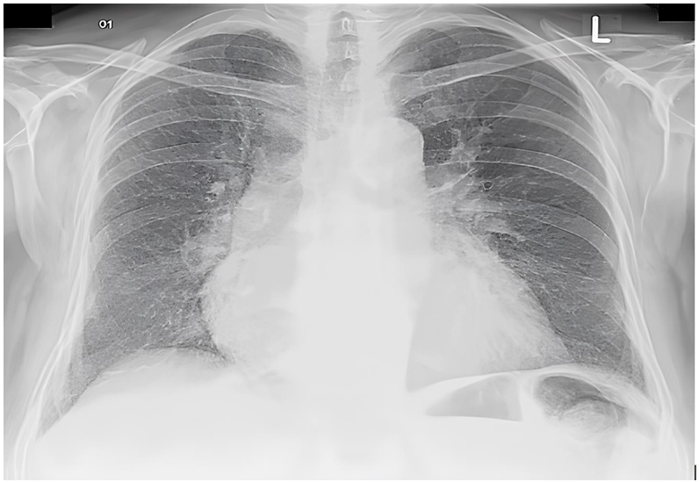

Homem, 65 anos, hipertenso e diabético, vai à emergência por dispneia súbita e dor

torácica intensa. Seus sinais vitais são: PA 170/110 mmHg, FC 92 bpm, FR 26 mpm, spO2 92% em

ar ambiente. Ao eletrocardiograma e à radiografia de tórax, tem-se os seguintes achados: